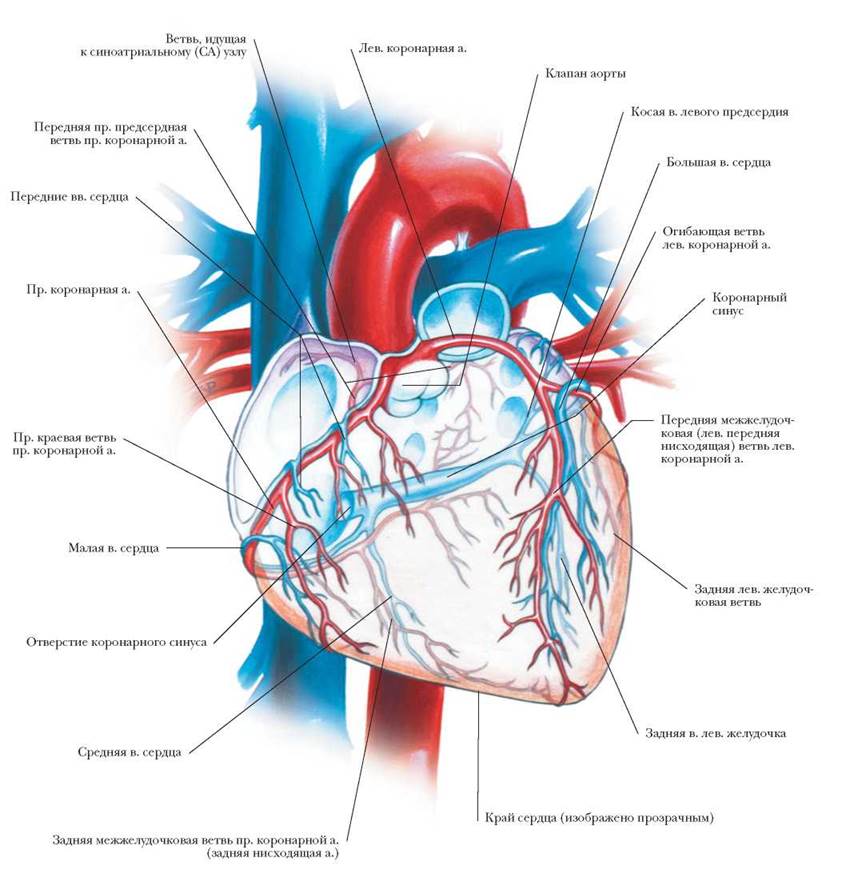

Анатомия коронарных артерий: КТ-изображения